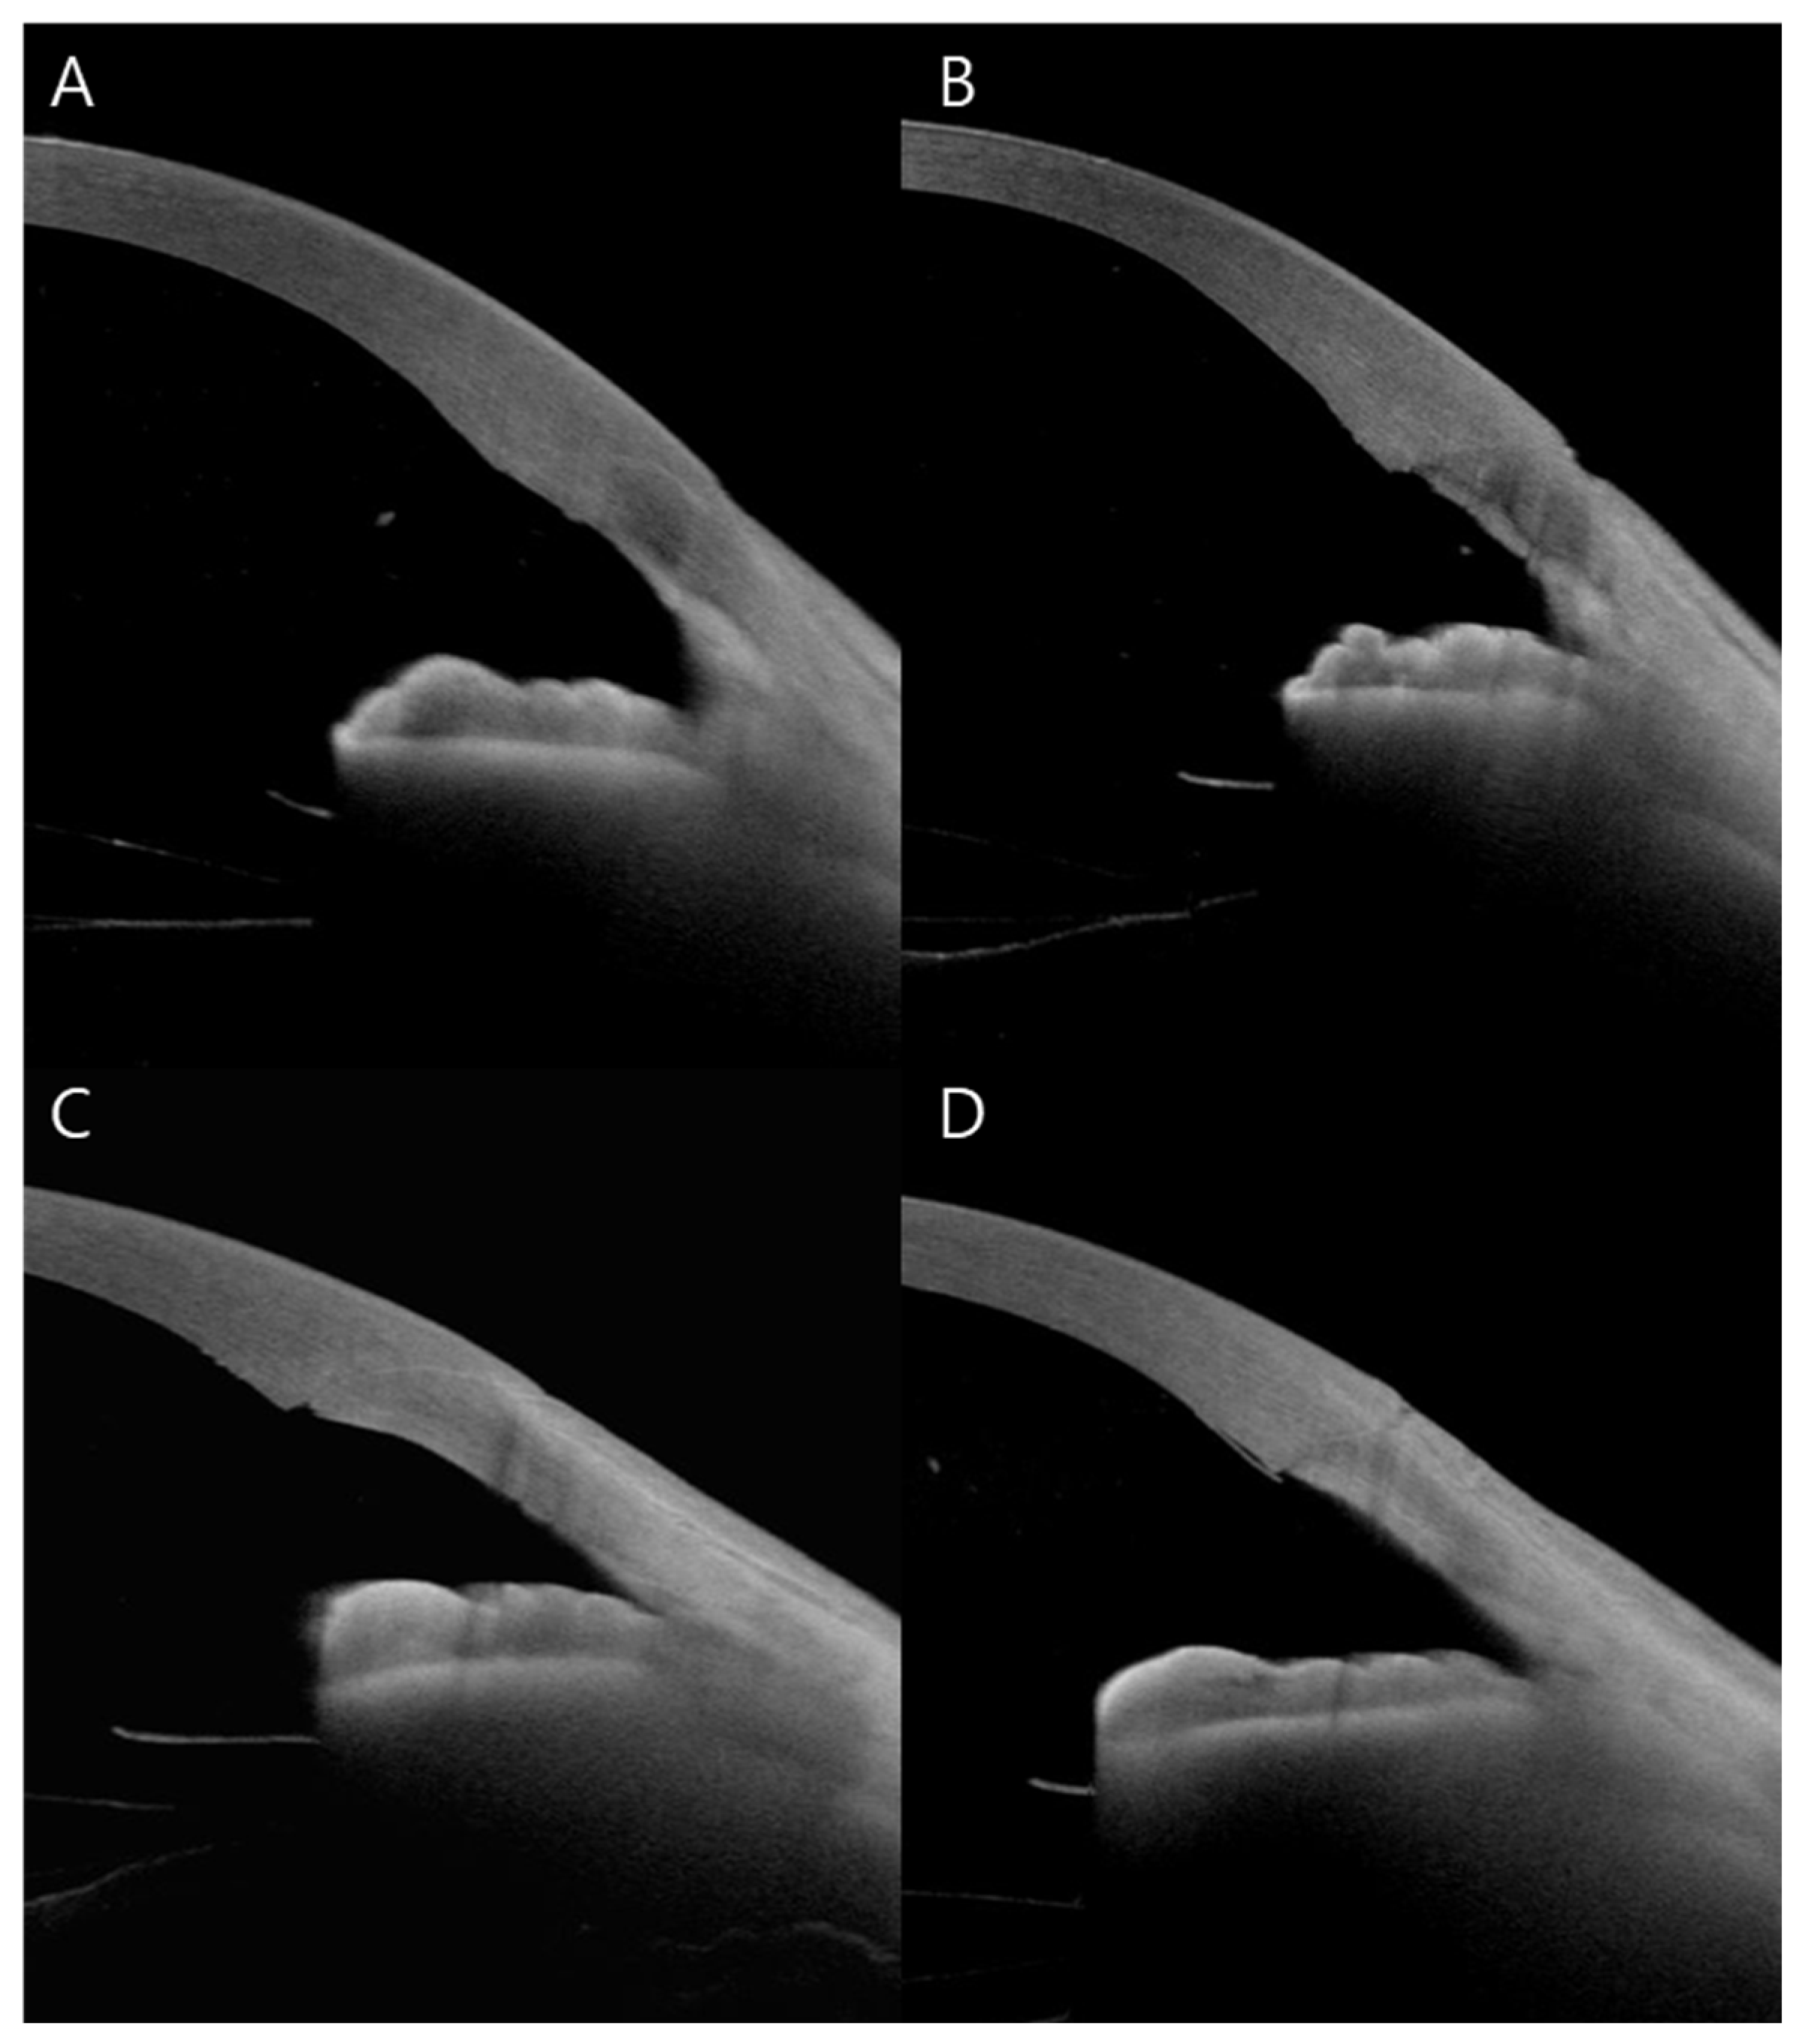

A total of 16 eyes of 16 patients underwent AS-OCT. Among these, four eyes (25%) demonstrated completely intact wound integrity. Epithelial gaping was observed in eight eyes (50%), endothelial gaping in five eyes (31%), local detachment of Descemet’s membrane in three eyes (19%), and endothelial misalignment in three eyes (19%). There were no cases of loss of wound coaptation (Figure 3).

Figure 3. AS-OCT images of CCIs immediately after surgery. All incisions were created using a two-plane technique. Representative images illustrate different wound healing states. (A) completely intact wound integrity, (B) endothelial misalignment with epithelial gaping, (C) endothelial gaping, (D) local detachment of Descemet’s membrane accompanied by epithelial gaping.